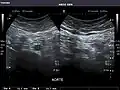

Abdominal Ultrasound (Full Exam)

STRUCTURED REPORT

(Technique: Transabdominal ultrasonography; Device: Toshiba Aplio XG)

Aorta: Visualized portions normal in caliber, 16 x 15 mm.

Aorta -